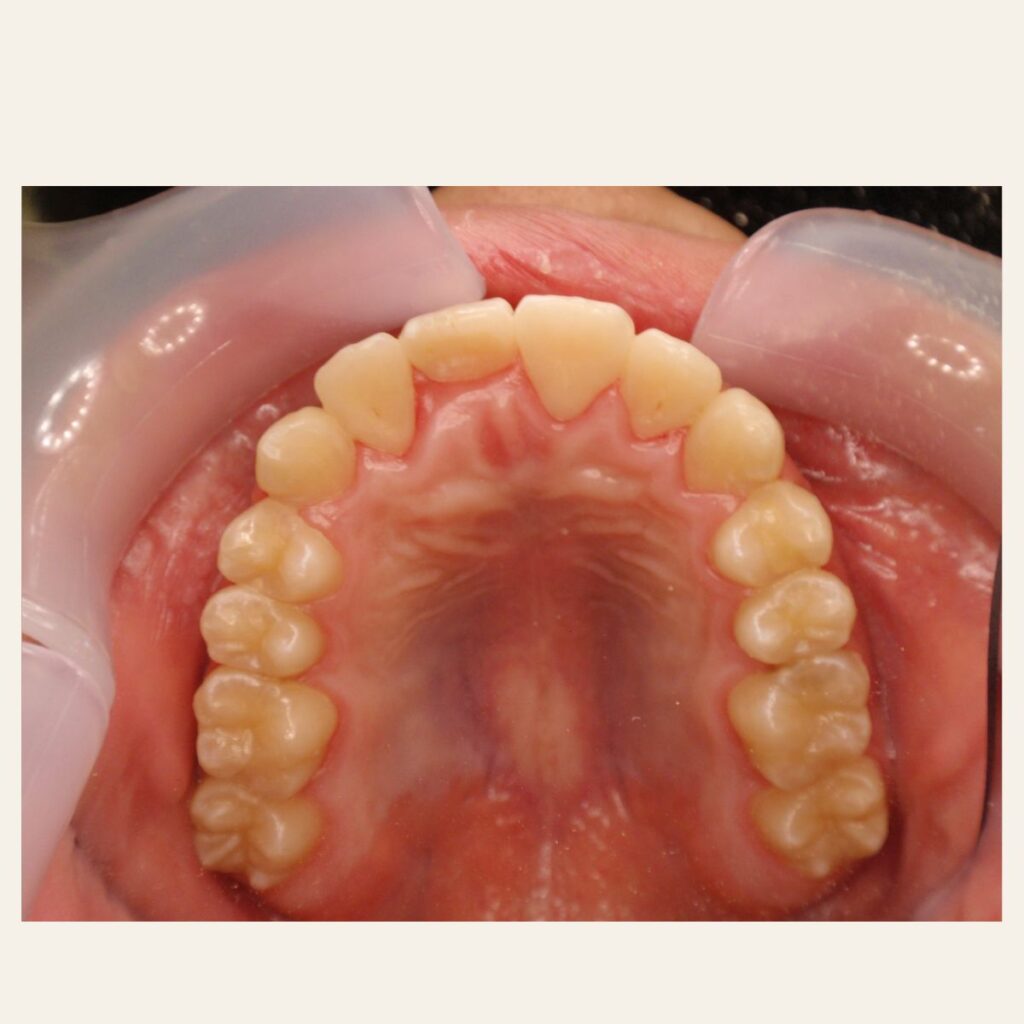

叢生の症例2(マウスピース矯正)

治療前後(BEFORE/AFTER)

| 年齢 | 40代女性、叢生 |

| 主訴 | 左前歯のガタガタ |

| 診断 | 叢生 |

| 治療方法 | 上下・マウスピース矯正(抜歯はしていません) |

| 治療期間 | 約1年 |

| 費用総額 | 660,000円(税込) |

| リスク・副作用 | 痛み/歯根吸収/歯肉退縮/後戻り など |

本症例では左側前歯が重なっている叢生状態でした。

若干の下顎前歯のガタガタも併せて治したいというご希望でした。

歯列のスペースを確保しかみ合わせも意識しながら歯並びを整えるため、下顎も含めて上下マウスピース矯正を用いて治療を行いました。

治療後は歯並びとかみ合わせが改善し、

見た目だけでなく歯磨きもしやすい状態になりました。

※虫歯・着色等の治療は矯正治療後に仕上げています。